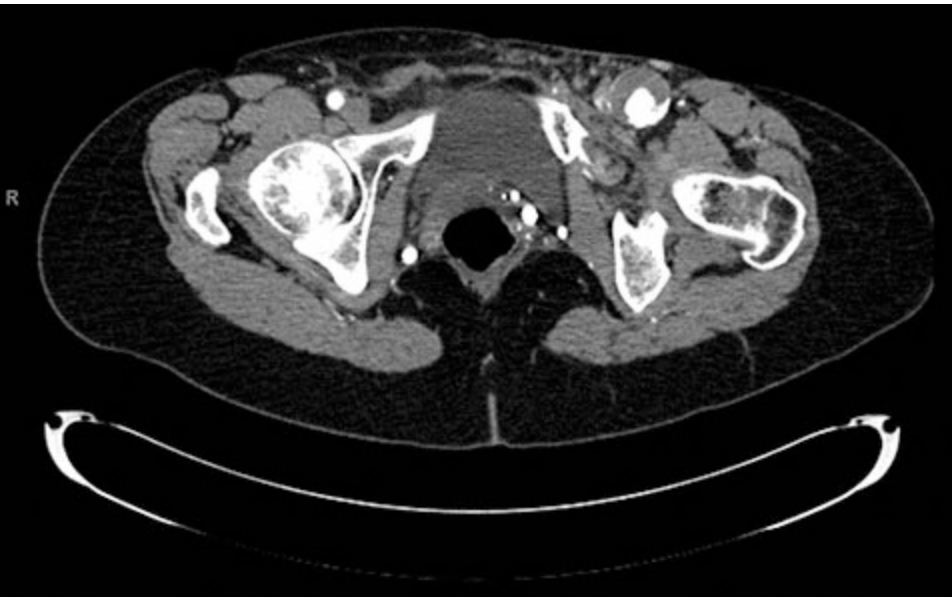

A 71-year-old man is brought to the emergency department because of a 1-week history of increasingly severe pain in his left third toe. During the past 36 hours, he has not slept because of the pain. He has coronary artery disease, hypertension, and hyperlipidemia. Six years ago, he had a myocardial infarction. He has never undergone an operation. His medications are ramipril, labetalol, and aspirin. Acetaminophen and ibuprofen have provided no pain relief. He smoked one pack of cigarettes daily for 40 years but quit 6 years ago. He appears uncomfortable. His pulse is 84/min, and blood pressure is 170/90 mm Hg. A 4-cm, pulsatile, nontender mass is palpated in the left inguinal region. The left third toe is necrotic and exquisitely tender to palpation; there is no erythema or drainage. Pedal pulses are 2+ on the left. The remainder of the examination shows no abnormalities. A CT scan of the abdomen and pelvis is shown. In addition to intravenous analgesic therapy, which of the following is the most appropriate next step in management?